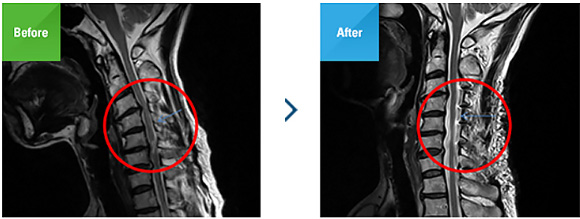

↑ 뚜렷한 불안정성은 보지 못하지만 오히려 경추의 운동 각도가 크게 변하지 않아요.역동적(dynamic)X선에서 불안정성(instability)은 관찰되지 않습니다.눈에 띄는 것은 의외로 목뼈 사이에 움직임이 거의 없는 것입니다.(이 부분이 앞으로 수술의 방향을 정할 때 큰 영향을 미치게 됩니다.여기에서 실시하는 검사는 두개에요.우선 CT는 후종 인대 골화증의 위치, 크기 그리고 형태에 대하여 보다 정확히 파악하고 치료 방향을 결정하는 데 결정적인 정보를 제공합니다.MRI는 후종 인대 골화증을 보는 것은 없으며 나중 종양 인대 골화증으로 압박된 신경의 위치, 압박의 정도 손상 정도를 확인하는데 도움이 됩니다.결국 수술 여부와는 관계 없이 CT와 MRI을 비교하게 됩니다.후 세로 인대 골화증에서는 CT와 MRI의 양쪽이 중요한 검사입니다.↑ 제3경추에서 제5경추에 이르는 후 세로 인대 골화증이 신경관의 대부분을 막고 있습니다.제4-5경추의 전방 경계가 서로 연결되고 있습니다.시상 면 영상(sagittal view)입니다.이 동영상에서 신경관을 점유하고 있는 후 종양인 메이저 골화증의 범위와 위치, 크기를 확인할 수 있습니다.후종 인대의 범위는 제3경추에서 제5경추까지이다(빨강 돈미 화살표), 신경관의 절반 이상을 차지하고 있습니다.특정의 위치에서는 신경관의 대부분을 차지하는 곳도 있다(오른쪽 사진)경추 척수의 압박과 손상이 크다고 예상됩니다.제4~5경추 간격( 노란 색 화살표)에서 척추 단체 간 전방 경계가 이어지고 있습니다.이 부분은 퇴행성 변화로 봐야 할지, 아니면 후방 구조물이 후 세로 인대 골화증 등에 움직임이 줄어드는 자연스럽게 유합 된 것은 아닐까(autofusion.↑ 제3경추체의 뒤에서 희미한 뼈화한 황색 인대와 제3-4경추에서 신경관의 오른쪽을 거의 가로막은 뼈화한 황색 인대가 확인됩니다.가장 심한 부분인 제3-4경추 부분의 단면 영상(axial view)입니다.제3경추의 뒤편(왼쪽 사진) 제3경추 척추체(vertebral body)와 거리가 멀고 얇은 뼈화된 뒤 세포종 인대가 확인됩니다.이런 형태는 일반적인 디스크나 협착증의 형태가 없습니다.우연히 이런 소견이 나오고, 뒤 세포종 인대 골화증이 발견되는 일이 많습니다.그러나 오른쪽 사진에서는 골화하고 신경관의 오른쪽 부분을 거의 막아 버린 뒤 세로인대 골화증이 눈에 들어갑니다.전방의 뒤 세포종 인대 골화증과 후방의 후궁(lamina)사이에 경추 척수(cervical spinal cord)이 심한 압박을 받고 있는 것이 예상됩니다.문제는 뒤 세포종 인대 골화증이 이렇게 크고도 굳이 제거하기는 어렵다는 것입니다.신경을 누르는 병변을 찾았으므로, 압박된 신경을 평가하기 위해서 MRI을 알아보겠습니다.↑ 경추 척수가 제3-4경추에서(적색 화살표) 심한 압박되어 있으며 척수의 음영이 주변보다 밝게 보입니다.외에도 여러곳에서 경추 척수가 압박되어 있습니다.우선 시상 면의 영상입니다.경추 척추는 제3-4경추 부분에서 붉은 화살표)가장 심한 압박되고, 그 아래의 부분에서도 압박되어( 노란 화살표들) 있습니다.그런데 특히 제3-4경추 부분의 척수를 보면 녹색의 화살표의 끝에 음영 변화(signal change)이 있습니다.물론 너무 선명하지 않지만 더 밝은 흰색으로(high signal intensity) 보입니다.척수 병증이 어려운 것이 치료도 어렵다, 척수 병증을 설명하는 것은 더 어렵고 그것을 환자와 보호자들에게 이해시키는 것은 더 어렵지만 치료의 방향을 결정짓는 것이 가장 어렵습니다.환자의 증세와 딱 맞는 음영 변화가 선명하게 있다면 또 모를까, 이 환자처럼 증상은 누가 뭐래도 척수 병증인데, 영상에서는 척수 병증의 존재에 대한 반론 불가능한 증거가 없는 경우가 많기 때문입니다.그러나 비록 매우 선명한 화상이 아니더라도 뚜렷한 증세와 함께 척수 병증이 일으키는 끔찍한 상황이 존재하는 경우는 척추 병증을 진단하게 됩니다.그 이유는 척수 병증은 만약 그 존재에 대해서 제대로 인지하지 못하고 지날 때 우리의 여생에 미치는 영향이 재앙에 이를 만큼 치명적이고 절망적이기 때문입니다.결론으로서 이 환자는 이 그림만으로도 척수 병증을 진단하는 것이 합리적이라고 생각됩니다.↑ 제 3-4 경추척수가 골화된 후종인대에 의해 (빨간 화살표) 압박을 받고 있습니다. 부담감은 주로 오른쪽에 집중되어 있습니다.제3-4경추의 단면 영상입니다.뼈화해서 커지고 오른쪽 신경관을 거의 막은 뒤 세포종 인대에 의해서 경추 척수가 압박되어 있으며, 그 부분의 척추는 신호 강도가 더 강한( 밝게) 보입니다.너무 선명한 고 신장 좋은 강도는 아니지만 이미 증상이 심한 후 종양의 대골화증, 이로 인한 신경 압박이 분명하기 때문에 척수 병증이 이 부분에 있다고 판단합니다.아니오, 판단해야 합니다.참고로 MRI영상과 CT화상을 비교하면 어느 화상에서 후 세로 인대 골화증의 크기와 모양을 잘 볼 수 있는지, 또 어떤 영상으로 압박된 신경과 그 변화를 잘 볼 수 있는지 알아요.한번 척수의 일부가 고 신호 강도에 보면, 경추 척수의 괴사(necrosis), 부종(edema), 또는 출혈(hemorrhage)등을 의심해야 합니다.적어도 외상의 과거력이 분명하지 않아 경추 척수 부분적인 괴사 혹은 부종으로 보입니다.여기서 분명히 이해할 필요가 있는 것은 치료의 목표는 이미 괴사한 부분의 재생에 따른 증상의 개선은 아닙니다.아직 괴사하지 않는 조직을 살릴 수 있는 환경을 만들어 증상이 개선될 여지를 만들 척수 병증 치료의 핵심입니다.↑ 제4-5 경추, 제5-6 경추, 제6-7 경추신경관에서도 후종인 대골화증에 의해 경추척수가 압박받고 있습니다. 4-5 경추, 5-6 경추, 6-7 경추 신경관입니다. 각 분절에서 경추척수가 제3-4경추만큼 신경관이 압박을 받는 것은 아니지만 경추척수가 조금씩 압박을 받으면서 그 모양이 타원형이 아니라 바나나형으로 바뀌고 있습니다.진단명은 후종인대 골화증과 그에 따른 척수병증분명히 진단된 것으로써 치료의 방법을 결정해야 합니다.여기서 우리가 집중해야 하는 것은 병의 원인과 위치입니다.후 세로 인대 골화증의 위치는 경추 척추체의 뒤쪽, 경추 척수의 전방에 있어 제거하는 것은 현실적으로 어렵습니다.그래서 뒤 세포종 인대 골화증의 경우는 병변을 제거하는 것이 아니라 신경의 후방 구조물인 후궁(lamina)의 형태를 바꾸고 신경이 지나는 공간을 넓게 펴고 줍니다.이를 후궁 성형술(laminoplasty)라고 합니다.최근 한 환자가 오는데 한 대학 병원에서 용기를 갖고 전부터 들어 몇가지 말에 전방 유합술(ACDF)를 하고 있었습니다.자, 증상이 바뀌지 않고 있는 것으로 검사를 하고 보니 뒤 세포종 인대 골화증은 전혀 제거하지 못한 상태에서 수술이 끝나고 있어서 깜짝 놀랐습니다.후 세로 인대 골화증 자체를 제거하는 것이 불가능한 것은 아니지만, 일반적으로는 앞쪽에서 제거하는 것이 불가능하다고 재차 확인되었습니다.그러나 굳이 제거하려면 앞쪽에서 들어가야 한다는 것도 원칙입니다.디스크 공간에 접근하는 전방식은술의 방법이 아니라 경추체(vertebral body)을 제거하면서 큰 인공 뼈(cage)을 삽입하는 큰 수술하면 됩니다.불가능한 것은 아니지만, 부정합이나 인접 부분 퇴행성 변화 등 더 큰 문제가 생각됩니다.그래서 수술을 계획할 때는 디테일에 짜야 합니다.우선 가장 심한 부분인 제2~3경추 사이에서 제2경추의 극돌기는(spinous process)손을 대고는 안 됩니다.그러나 필요에 응하고 극 돌기의 기저부(base)의 내면만 갖추는 일도 있습니다.이를 돔 성형술(dome plasty)라고 합니다.제3요추 후궁의 형태를 성형할 수도 있겠습니다만, 너무 심한 부분에서는 후궁 1개 정도를 완전히 제거하는(total laminectomy)방법이 좀 더 간단하고 확실한 방법입니다.위에서 설명한 이분의 목은 거의 움직임이 없는 정도에 일부 유합 되어 있으며 가시 돌기 하나쯤은 큰 탈 없이 제거할 수 있습니다.그 아래, 제3-4경추 제4-5경추 제5-6경추에서 척수 병증이 발견되거나 신경이 심하게 압박된 적은 없습니다.하지만 이곳을 함께 감압해야 하는 이유는 압박이 심한 곳의 후궁을 감압하면(decompression)신경이 이동하게 됩니다만, 그 과정에서 함께 감압되지 않은 상하 분절 측에서 신경이 조금 부러져며 압박될 가능성이 있기 때문입니다.이때 병이 심한 점의 후궁은 완전히 끄고, 그렇지 않은 곳의 후궁은 일부만 끊고 한쪽으로 굽도록 하겠습니다.자른 편에는 금속판과 나사로 고정합니다.환자의 후 종양인 대골화증은 오른쪽이 더 심해서 오른쪽을 잘라내고 들어가는 방법(Open door laminoplasty)을 실시합니다.그리고 마지막 부분인 제7경추 위에 돔 성형술을 함께 합니다.수술 계획은 제2경추 돔 성형술 제3경추 후궁 전 절제술 제4경추 제5경추 제6경추 후궁 성형술 제7경추 돔 성형술로 결정하게 되었습니다.사실 환자는 유튜브를 보고 수술을 받기에 입국한 상태였습니다목(경추)수술은 항상 전신 마취입니다.수술 시간은 3시간 정도 걸렸습니다.수술 후 환자는 대개 목의 통증을 심하게 호소하는 경향이 있습니다.수술 범위가 제2경추에서 제7경추에 이르는 것으로 후두부에서 등이 시작 부분까지 피부를 절개하고 근육을 좌우로 벌리고 수술하지 않으면 안 되니까요.목은 항상 피가 많이 나옵니다.그래서 경우에 따라서는 수혈이 필요하게 될 수도 있습니다.수술 직후 X선을 촬영하겠습니다.몸에 이물질( 작은 철판과 나사)을 삽입한 경우는 미루지 말고 최대한 빨리 영상을 확인할 필요가 있습니다.↑ 세번째 경추 극돌기가 안 보이(적색 화살표).제4경추 제5경추 제6경추의 오른쪽에 작은 철판과 나사가 있어 성형된 후궁을 고정하고 있습니다( 노란 색 화살표).먼저 눈에 띄는 것은 금속판 3장과 작은 나사입니다.제4경추 제5경추 제6경추 후 활의 오른쪽을 끄고, 반대 측으로 접었다 펴고 수술이므로 자른 측인 오른쪽만 금속으로 고정했습니다.나사는 생각보다 사이즈가 작습니다.그리고 간과하기 쉬운 것이, 제3경추 극돌기가 사라진 것입니다.붉은 화살표는 제3경추가 있던 곳입니다.완전히 제거하고 사라졌습니다.나는 가능하면 수술 하루 만에 MRI나 CT를 촬영하지만 후궁 성형 수술을 하신 분은 아파서 하루 2일 정도는 미룹니다.통증이 심합니다.다음 사진은 수술 3일째에 촬영한 영상입니다.모두 가장 왼쪽 사진은 수술 후 MRI가운데 사진은 수술 후 CT, 오른쪽 사진은 수술 전 MRI입니다.비교 때문에 함께 배치했습니다.시상 면 화상에서 개괄적인 변화를 수술 전과 비교할 수 있습니다.우선 수술 전/후의 사진을 경추 척수의 입장에서 비교하면 수술 전에는 척수가 여유 없이 겨우 신경관을 지나는데, 수술 후에는 전후에 여유 공간이 생겼습니다.CT에서도 이 분 후 종양 인대는 전혀 제거하지 않습니다.그러나 제3경추의 극돌기가 사라지고, 제4경추에서 제6경추는 극돌기가 뒤로 옮겨지고 있습니다.이때 후궁 성형술을 한 후에 심한 돌기를 자르고 다듬어서 길이도 짧아집니다.↑ 수술 전/후의 영상에서 신경관과 경추 척수의 크기가 매우 커졌습니다.제3경추의 후궁이 완전히 사라지고( 노란 색 화살표)가능합니다.제3-4경추에서의 단면입니다.가장 눈에 띄는 것은 경추 척수의 크기입니다.수술 전에는 망해서 압박 받고 있는 것이 잘 보이지만 수술 후에는 뼈화한 뒤 세포종 인대가 그대로 남아 있는데, 제3경추의 후궁이 완전히 제거되고( 노란 화살표)신경관의 뒤쪽 공간이 너무 넓어지고 신 경관과 경추 척수가 너무 넓어지고 있습니다.오히려 이러한 변화가 있어 다시 관류 손상(reperfusion injury)를 수술 전에 미리 설명합니다.CT에서도 후궁이 통째로 사라지고 있는 것으로 나타납니다.↑ 수술 전/후 영상에서 신경관이나 경추척수의 크기가 매우 커졌습니다. 제3경추의 후궁이 완전히 사라지고(노란 화살표) 가능합니다. 제3-4 경추에서의 단면입니다. 가장 눈에 띄는 것은 경추척수의 크기입니다. 수술 전에는 찌그러지고 압박받는 게 잘 보이는데 수술 후에는 골화된 후종인대가 그대로 남아 있는데 제3경추 후궁이 완전히 제거되고 (노란 화살표)신경관 뒤쪽 공간이 너무 넓어져서 신경관과 경추척수가 굉장히 넓어져 있습니다. 오히려 이러한 변화가 있기 때문에 재관류 손상(reperfusion injury)을 수술 전 미리 설명합니다. CT에서도 후궁이 통째로 사라진 것을 알 수 있습니다.↑ 수술 전/후 영상에서 신경관이나 경추척수의 크기가 매우 커졌습니다. 제3경추의 후궁이 완전히 사라지고(노란 화살표) 가능합니다. 제3-4 경추에서의 단면입니다. 가장 눈에 띄는 것은 경추척수의 크기입니다. 수술 전에는 찌그러지고 압박받는 게 잘 보이는데 수술 후에는 골화된 후종인대가 그대로 남아 있는데 제3경추 후궁이 완전히 제거되고 (노란 화살표)신경관 뒤쪽 공간이 너무 넓어져서 신경관과 경추척수가 굉장히 넓어져 있습니다. 오히려 이러한 변화가 있기 때문에 재관류 손상(reperfusion injury)을 수술 전 미리 설명합니다. CT에서도 후궁이 통째로 사라진 것을 알 수 있습니다.↑ 제4경추 제5경추 제6경추의 단면입니다.신경관이 2배 이상 확산되어 후궁의 오른쪽에 금속판과 나사가 삽입되고 고정되었습니다.위 사진은 제4경추에서 제6경추의 단면입니다.한결같이 신경관을 이루는 후궁의 오른쪽은 끊기고 반대편으로 꺾어 있고, 그 공간은 금속판과 작은 나사로 고정되어 있습니다.신경관은 대략 2배 이상 넓어지고 충분한(혹은 그 이상 감압이 시행되고 있습니다.환자의 연령이 젊고 회복이 너무 빨랐어요.그래도 수술 다음 날까지 목의 통증이 심해서 내가 신경통이나 감각이 얼마나 좋아졌는지 듣기가 미안한 정도였지요.며칠 지나서 목의 통증이 좋아졌고 결국 환자의 손바닥에 저린 증상이 일부 남아 있는데, 팔 저림은 완전히 사라지고 몸통의 감각 이상도 완전히 사라졌대요.그냥 걸을 때에 다리 힘이 좀 떨어지는 것은 남아 있다고 합니다.너무 근육을 깊이 만지는 수술이기 때문에 입원은 1주 정도 있었습니다.항생 물질을 쓰지 않으면 안 되니까요.지금은 2개월 만에 미국에 돌아가시는 바람에 SNS상에서 안부를 묻고 있는데 조금씩 호전 중이라고 합니다.후종 인대 골화증을 진단하는 것은 그리 어렵지 않습니다.병을 이해시키고 계획을 공유하는 것이 더 어렵습니다.그러나 치료 하는 것은 더 어렵습니다.희귀 병이므로 의사조차 경험과 치료를 쉽게 권하는 것은 쉽지 않습니다.그냥 편하게 대학 병원에 보내는 것도 한 방법이긴 하지만 믿고 찾아온 환자를 그렇게 가는 것은 정말 제 능력 밖이 아니면 피하려고 생각합니다.후궁 성형 수술은 나에게는 어려운 수술은 아닙니다.단지 육체적으로 힘들어 수술 후에 피곤해져수술에 불과합니다.실제로 나는 이 수술을 할 때는 손에 힘을 많이 넣어야 하므로 손이 입덧기 쉽습니다.물론 환자는 더 아파서 힘들겠지만.칼을 쥐고 외과계 의사(surgeon)에는 필요한 수술을 필요한 환자에게 제공할 수 있다는 사실만으로도 뿌듯합니다.한 친한 의사의 친구는 왜 이런 큰 수술을 하냐고 그냥 대학 병원에 보내어 버리기 쉬운 수술 상대적으로 쉽고 문제가 적은 수술만 해도 좋다고 말합니다.그런데 제가 능력이 충분히 있고, 환자의 신뢰가 있으면 얼마든지 이런 수술을 합니다.비록 몸이 아파서도요.아직은…척추 병증 수술 시 참고하기https://blog.naver.com/withjjang/222553137937후궁 성형술은?https://blog.naver.com/withjjang/222575113212마디세상병원 서울특별시 중랑구 동일로 890 예약마디세상병원 서울특별시 중랑구 동일로 890 예약마디세상병원 서울특별시 중랑구 동일로 890 예약